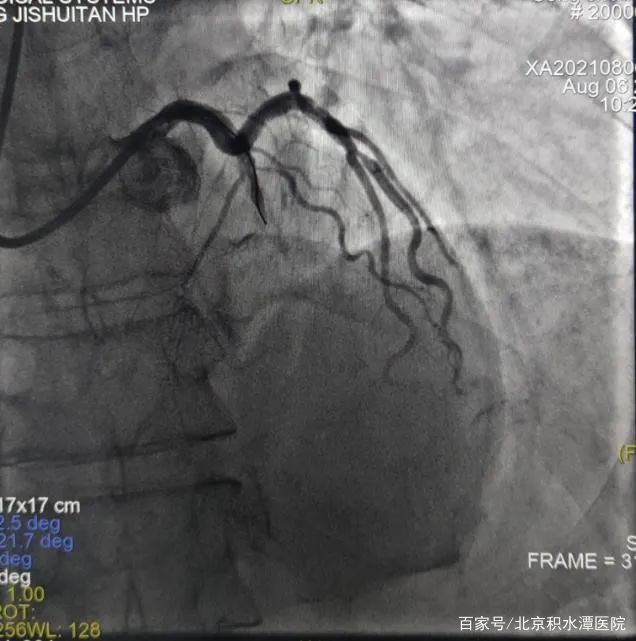

但在上台后,发现3个月过后,左前降支血管已经完全闭塞,手术难度远远超出预期,无法判断血管走行和方向。所以决定采用微量造影剂的办法进行介入治疗。刘教授凭借经验,在只应用少许造影剂的情况下,不断更换导丝进行尝试后,终于通过闭塞病变到达血管远端。导丝通过闭塞病变后,不再使用造影剂,使用IVUS检查发现,闭塞处有严重钙化斑块。通过IVUS明确支架植入位置和大小,最终成功植入支架。手术过程共使用造影剂约20ml。术后监测患者血肌酐,无明显改变并且处于稳定状态。患者也高高兴兴地出院了。

在对李女士的治疗过程中,刘巍教授在患者的第一次冠状动脉造影的影像指导下,经过远端桡动脉入路,将指引导管放置在右侧冠状动脉开口,导丝送至血管远端,但是由于患者病变弥漫,狭窄严重,并且开口就有病变,指引导管稍微深插就会出现压力下降和心电图ST段抬高,手术的难度超出预期。这时使用IVUS进行血管内超声检查,结果显示,右冠状动脉中段最小管腔面积仅2.0mm2,并且可见超声衰减斑块和高负荷脂质斑块,并且病变比预想的还要弥漫和严重。刘教授团队根据边支定位以及IVUS导管标记点定位,对狭窄病变进行充分预扩张,复查IVUS提示扩张效果满意后,根据IVUS定位精准地植入了两枚支架,再次复查IVUS提示支架膨胀及贴壁良好,无边缘夹层等情况。手术过程顺利,全程未使用一滴造影剂就成功完成了支架的植入。术后患者没有出现任何不适。手术过程不到30分钟,患者术后症状立刻缓解。第3天就出院了。

但在上台后,发现3个月过后,左前降支血管已经完全闭塞,手术难度远远超出预期,无法判断血管走行和方向。所以决定采用微量造影剂的办法进行介入治疗。刘教授凭借经验,在只应用少许造影剂的情况下,不断更换导丝进行尝试后,终于通过闭塞病变到达血管远端。导丝通过闭塞病变后,不再使用造影剂,使用IVUS检查发现,闭塞处有严重钙化斑块。通过IVUS明确支架植入位置和大小,最终成功植入支架。手术过程共使用造影剂约20ml。术后监测患者血肌酐,无明显改变并且处于稳定状态。患者也高高兴兴地出院了。